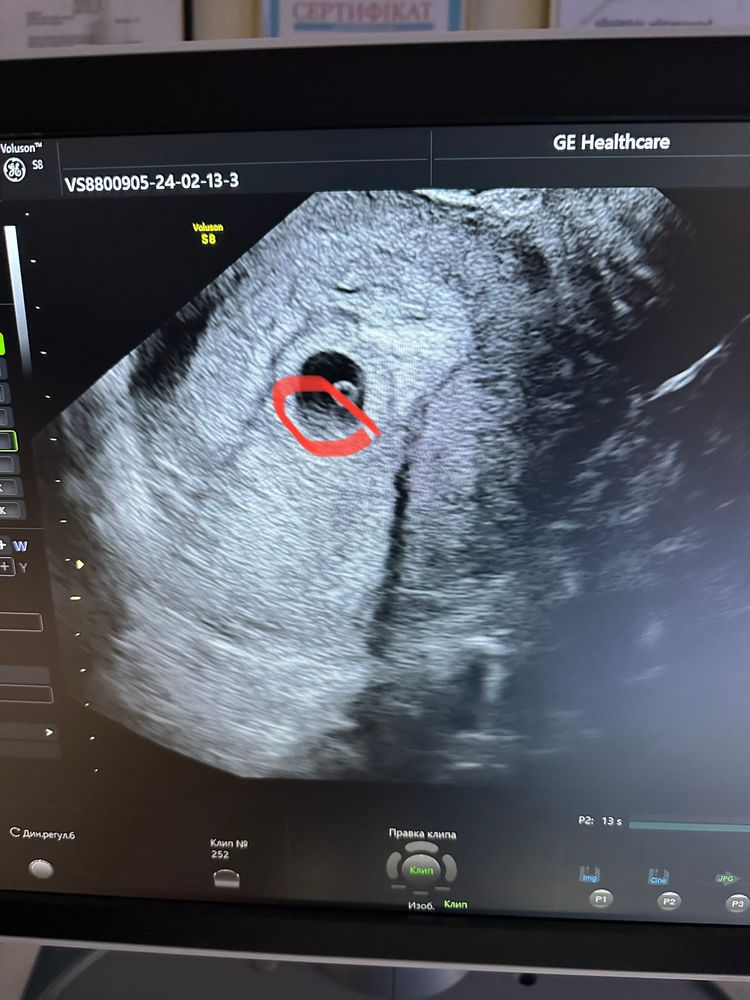

Елена, не подскажите, что это такое на узи? Под ЖМ Изображение Изображение